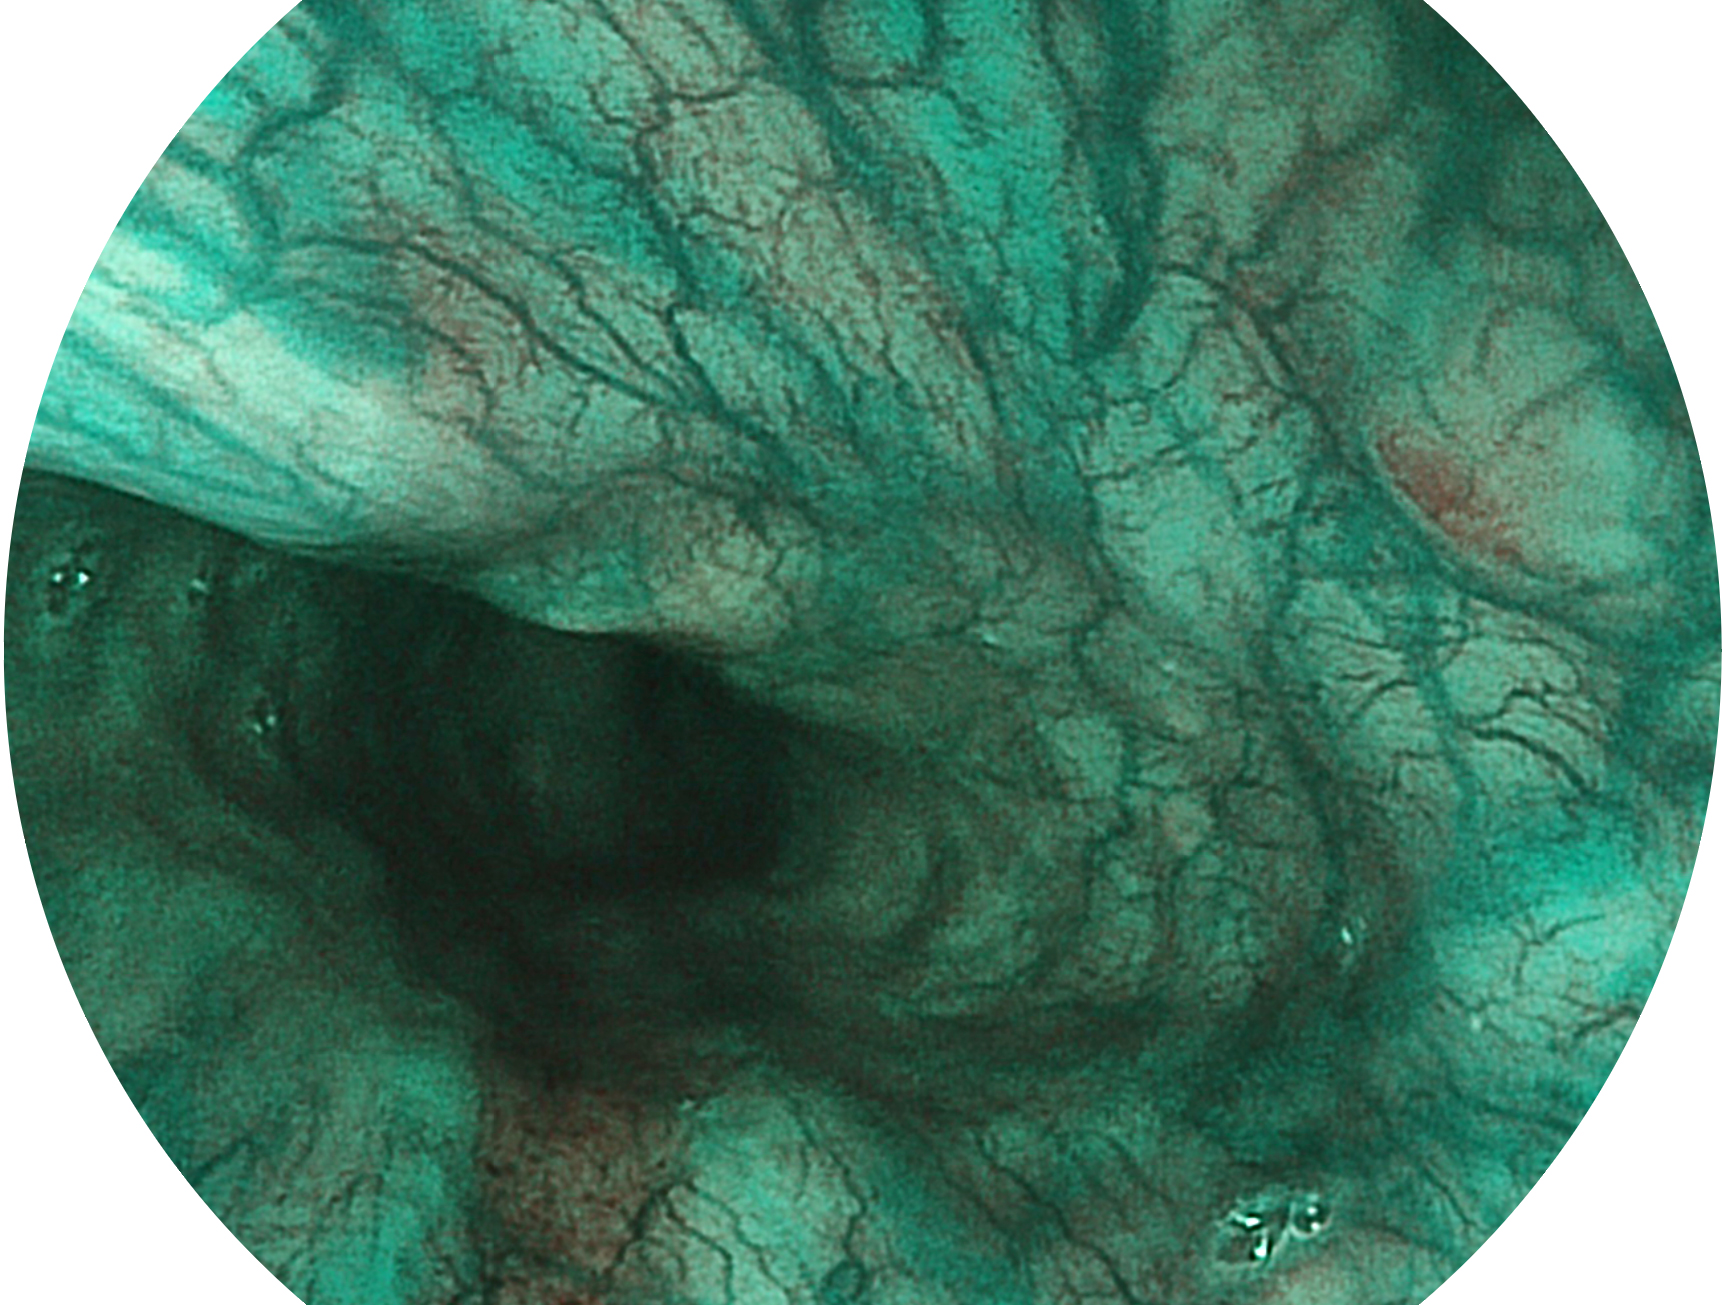

• 白光图像 SFI图像

SFI技术是结合特定光谱照明与数字光谱滤波,实现高亮度特殊光成像。染色模式下,不改变粘液、食物残渣、粪液等基本颜色,在保持与白光照明相似的图像色调的同时突显了图像颜色的红白对比度,且在远距离观察的情况下具备与普通白光模式相同的图像亮度,有助于消化道疾病的大范围扫查和早癌筛查。